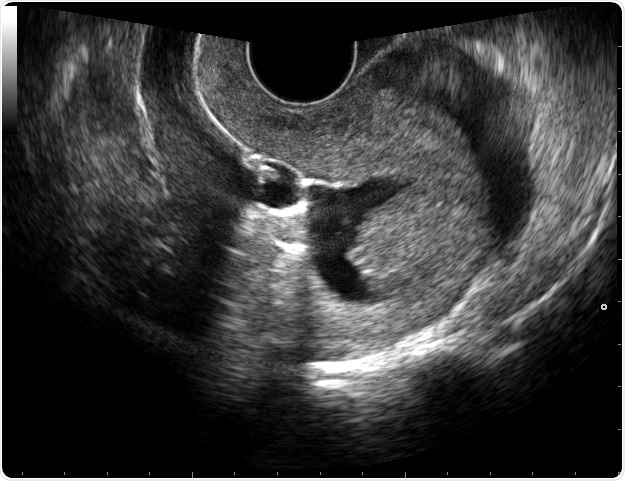

Sonohysterography. Sonohysterography is a technique to image the uterine cavity. Sterile saline is infused through a catheter to distend the uterine cavity. This allows seperation of contours of endometrium from the pathology. Attribution: © Nevit Dilmen

Under normal circumstances, the saline distends the uterine cavity (the walls of which typically touch each other) to produce a narrow dark area on the screen, surrounded by a white stripe which represents the endometrium (the inner epithelial lining of the uterus) on both sides of the cavity.

Various lesions which disturb this symmetrical appearance may appear during this visualization, such as adhesions (when the uterine walls are stuck together by scar tissue) bridging the dark central area, polyps as hyperechoic (white) areas with a narrow attachment point on the uterine wall at one area, and endometrial thickening (with enlargement of the white stripe surrounding the dark central area).